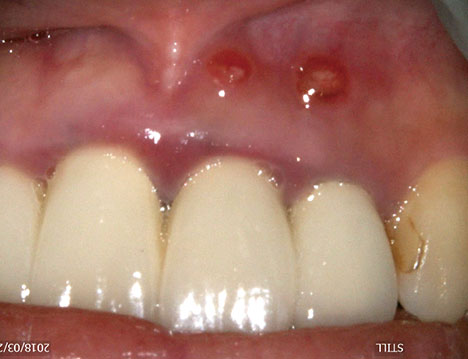

• ・レーザーを用いた破折ファイルの除去

• ・根尖孔外ガッタパーチャ(GP)除去、搔爬